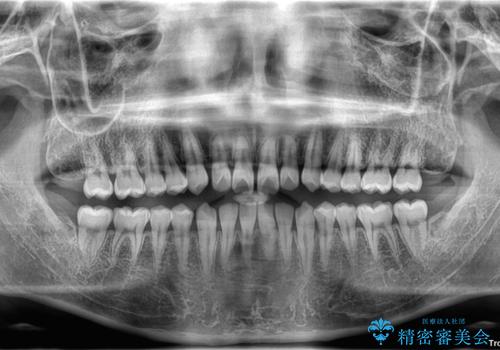

- 「前歯のすきっ歯が気になる」「食べ物が歯の間に詰まりやすい」とのお悩みで来院された20代男性の患者様です。

歯と歯の間に隙間がある**空隙歯列(すきっ歯)**は、見た目の問題だけでなく、食片圧入による歯肉の腫れや、隣接面う蝕のリスク増加につながることがあります。

診査により舌突出癖が認められました。この癖は、すきっ歯の原因となるだけでなく、矯正後の後戻りリスクを高めます。